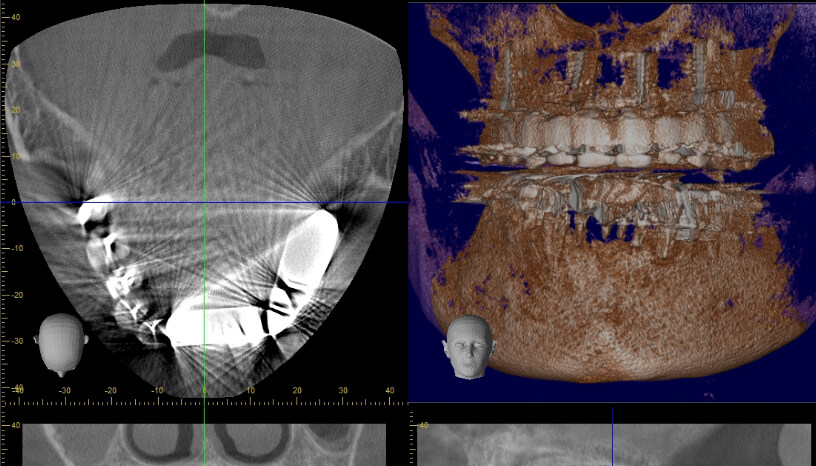

安全で正確な診断のための最新型CTを導入しています。CTというのは骨の状態を三次元で検査できる最新設備です。顎骨には神経や血管が通っていて、安全に治療を行うには不可欠な設備です。日本の歯科医院でCTを常備している医院は10%未満と言われていますが、インプラントを頻繁に行っている医院では確実に保有している設備です。最初のカウンセリングから終了後までいつでも撮影が可能です。

• レントゲン写真

画像が鮮明なため、的確な診断ができます。

3次元で診断できるため、安全性が高くリスクの少ない治療が行えます。